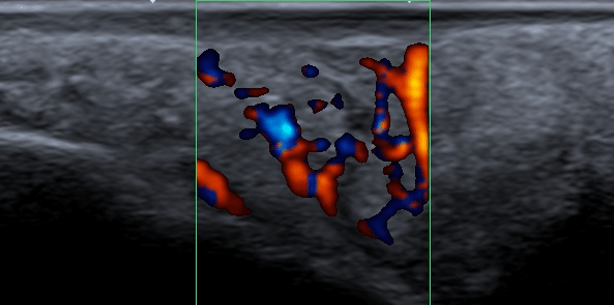

Die Fallbeschreibung soll dazu anregen über Möglichkeiten der Ultraschallkontrolle im Mundraum nachzudenken. Leider sind die heute gängigen...

Die Fallbeschreibung soll dazu anregen über Möglichkeiten der Ultraschallkontrolle im Mundraum...